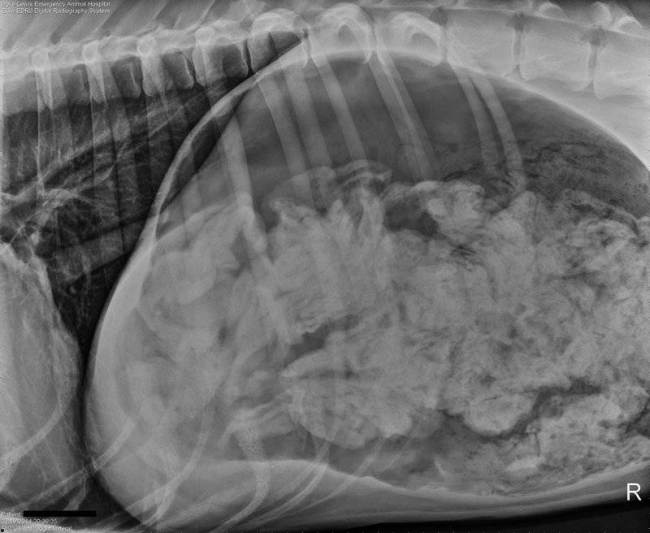

Το καημένο το σκυλί δεν μπορούσε να αναπνεύσει καλά ενώ είχε τάση για εμετό...

Οι ιδιοκτήτες του σκύλου το μετέφεραν αμέσως στην κλινική προκειμένου να του γίνουν οι απαραίτητες εξετάσεις.

Τελικά αποδείχτηκε ότι το σκυλί είχε μέσα στο στομάχι του ένα μικρό θησαυρό από... 43 κάλτσες!

Χρειάστηκε μία επέμβαση διάρκειας δύο ωρών για να μπορέσει να καθαριστεί το στομάχι του σκύλου ράτσας Great Dane (Μεγάλος Δανός αν προτιμάτε).

Προφανώς ο μεγαλόσωμος σκύλος το είχε δει σαν παιχνίδι να μασουλάει τις κάλτσες του αφεντικού του και στο τέλος τις κατάπινε!